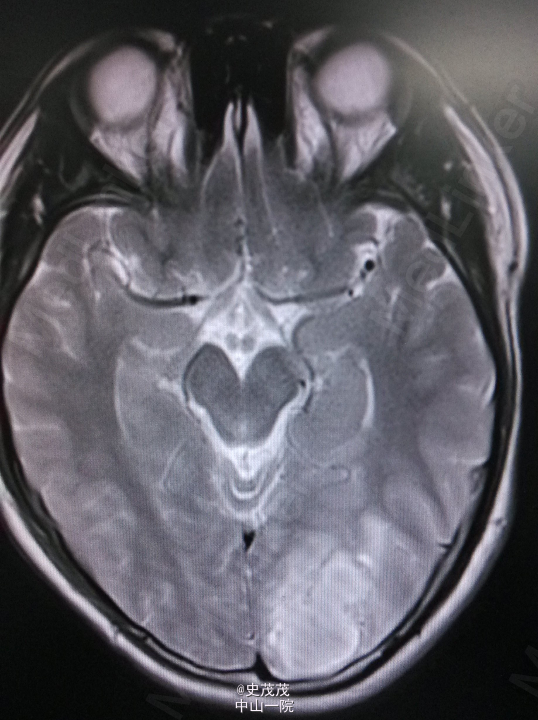

入院查体:神清,对答切题,记忆力及智力粗测正常,双侧瞳孔等大等圆,直径约2.5mm,对光反射灵敏,伸舌居中,耳鼻无异常分泌物,颈软,无抵抗,Kernig Sign(-),粗侧左眼视野变窄,其余颅神经检查未见明显异常,四肢活动好,肌力Ⅴ级,肌张力正常,生理反射存在,病理反射未引出。 辅助检查:CT:左侧枕顶叶片状高密度影伴周围低密度影,病灶范围约2.3cm×3.5cm×34cm,内见钙化灶。颅内动脉VR、MIP重建显示:左侧枕顶叶可见团状异常血管影,部分血管壁可见钙化斑,有左侧大脑中动脉供血。考虑左侧枕顶叶血管畸形并出血,建议复查。头颅DSA提示未看到输出静脉,需鉴别动静脉畸形及肿瘤。 头部MR增强扫描+头部血管扫描:左侧枕顶叶团块状异常信号影,大小约3.6×2.4×3.4cm,T1WI呈高低混杂信号,T2WI呈高信号,周围可见大片水肿区,增强后病变边缘有小片状强化影,肿块内见粗大血管影,肿块血管与邻近大脑中动脉、大脑中浅静脉关系密切。诊断提示左侧枕顶叶病变,考虑肿瘤与血管畸形鉴别,前者可能性大,合并出血,建议进一步检查